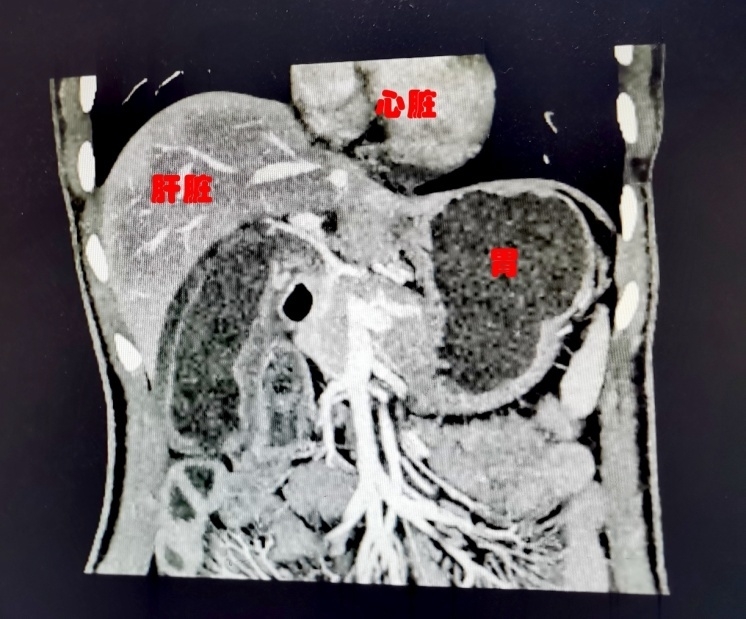

刘先生的腹部CT图像

年近五旬的刘先生便是一位“镜面人”。日前,他因胆囊结石住进了德阳市人民医院肝胆胰外科,医生在检查中发现,他的病情不算十分严重,但五脏六腑全都反着长。这也是近二十年来,该医院出现的唯一一例“镜面人”。

据悉,因手术使用的内镜器械根据通常人体内脏位置设计,因此面对“镜面人”,手术时需要“逆向思维”,克服反向进镜、反位放射图像、取石方向相反等诸多不利因素,操作难度较大。为此,医院为刘先生制定了详细的手术方案,并由德阳市人民医院院长、肝胆胰外科专家麦刚亲自主刀进行了标准化示教手术。